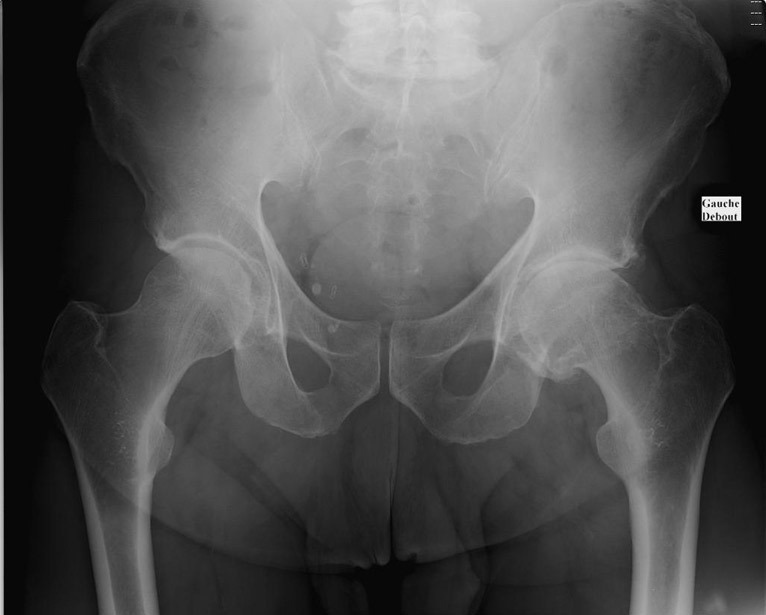

Monsieur M. vous rapporte une plainte au niveau de sa hanche gauche. Initialement ses douleurs étaient simplement à type de gêne, apparues il y a deux ans, sans traumatisme évident à l’anamnèse. Actuellement ces douleurs peuvent le maintenir alité les mauvais jours. Au réveil, il doit patienter quelques minutes assis avant de se lever, avec nécessité de se « dérouiller » avant de pouvoir « s’activer ». Parlant justement du sommeil, sa femme vous dit que cette douleur le réveille souvent lorsqu’il se retourne dans le lit. Il sort de moins en moins, ne peut plus jardiner et est devenu dépendant de son épouse pour les trajets, la conduite lui étant devenue impossible. Vous estimez son périmètre de marche à quelques centaines de mètres, les douleurs apparaissant très rapidement à la marche.